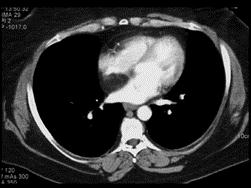

问题 女,35岁,心前区不适,无发热及呼吸困难,请结合CT图像,提出最可能的诊断 ( )

选项 A.脂肪肉瘤 B.脂肪瘤 C.心包憩室 D.心包囊肿 E.心包脂肪垫

答案 B